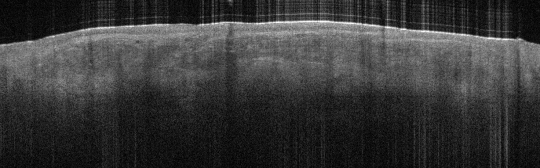

VA54: Left Superior Temple, Adjacent, Normal